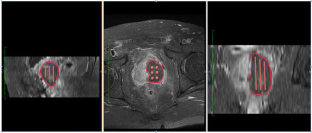

Vascular targeted photodynamic therapy (VTP) with WST11 is a novel non-thermal focal treatment for localized prostate cancer that has shown favorable and early efficacy results in previously published studies. In this work, we investigate the efficiency of automatic dosimetric treatment planning. An action model established in a previous study was used in an image-guided optimization scheme to define the personalized optimal light dose for each patient. The calculated light dose is expressed as the number of optical cylindrical fibers to be used, their positions according to an external insertion grid, and the lengths of their diffuser parts. Evaluation of the method was carried out on data collected from 17 patients enrolled in two multi-centric clinical trials. The protocol consisted of comparing the method-simulated necrosis to the result observed on day 7 MR enhanced images. The method performances showed that the final result can be estimated with an accuracy of 10%, corresponding to a margin of 3 mm. In addition, this process was compatible with clinical conditions in terms of calculation times. The overall process took less than 10 min. Different aspects of the VTP procedure were already defined and optimized. Personalized treatment planning definition remained as an issue needing further investigation. The method proposed herein completes the standardization of VTP and opens new pathways for the clinical development of the technique.